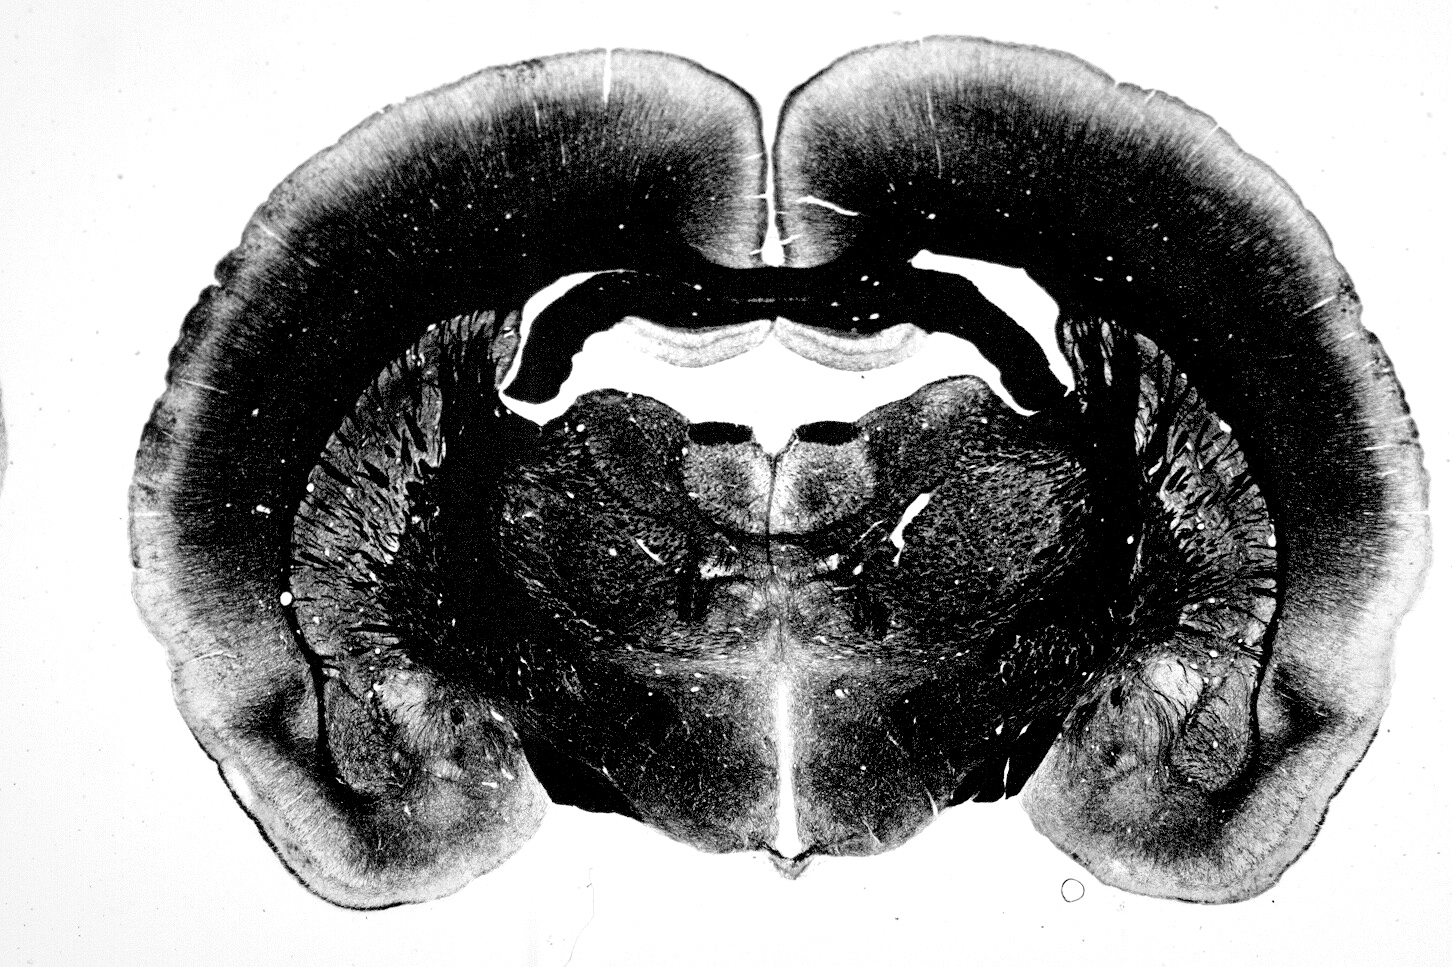

La hipótesis clásica de diferenciación sexual del cerebro establece que las hormonas gonadales del periodo crítico perinatal son las responsables de las diferencias neuroquímicas y citoarquitectónicas del cerebro de machos y hembras. Sin embargo, en los últimos 20 años la evidencia indica que los genes de los cromosomas sexuales tienen una participación directa en muchas diferencias sexuales no atribuibles a la exposición hormonal. GABA es el principal neurotransmisor inhibitorio en el sistema nervioso central adulto, sin embargo, durante el desarrollo ejerce acciones tróficas a través de la apertura de canales de calcio dependientes de voltaje. Resultados previos de nuestro laboratorio indican que existen diferencias sexuales en la respuesta de los receptores GABAA de neuronas hipotalámicas inmaduras.

Los cultivos neuronales de machos presentan una mayor cantidad de células que responden con excitación al GABA comparados con cultivos de hembras; y efectos similares se observan en la magnitud de la respuesta. Sorprendentemente, estas diferencias son independientes del tratamiento con testosterona. Nuestros resultados sugieren una distinta velocidad de maduración del sistema GABAérgico entre machos y hembras, que no se debe a la exposición a hormonas gonadales del periodo crítico. Probablemente el distinto complemento cromosómico sexual de machos (XY) y hembras (XX) puede explicar éstas diferencias. A través de ratones transgénicos (Four Core Gentopyes), cultivos primarios de neuronas hipotalámicas, calcium imaging, electrofisiología, morfometría, biología molecular y bioquímica estudiamos esta apasionante etapa del desarrollo ontogenético.